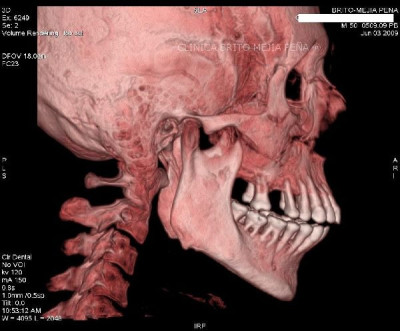

Detalle óseo